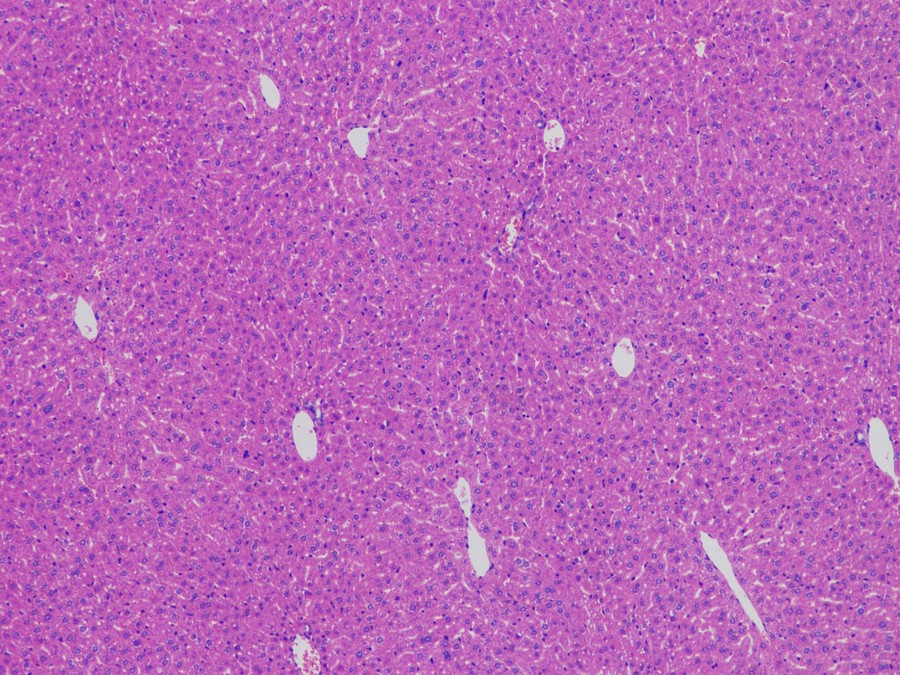

ML31下的正常肝细胞

肝脏主要由肝细胞组成,正常的肝脏HE染色切片在镜下呈现为绵密的肝细胞,细胞核清晰可见且形状比较规则,细胞间有少量不规则的空洞区域。